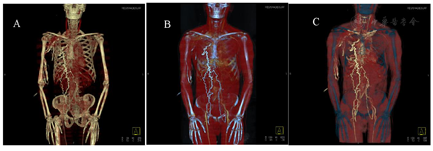

患者男,66岁,胸壁腹壁表浅静脉曲张半年,脸肿1个月余,随后行上腔静脉CT血管成像。

对比剂延扩张的胸壁以及腹壁表浅静脉,分别回流至双侧髂静脉,顺下腔静脉回流至心脏。其中奇静脉和肋间静脉也有扩张和对比剂充盈。上腔静脉中段显示局限性狭窄,接近闭塞,致使大量回流静脉扩张并逆流至髂静脉回流至心脏。

CT静脉血管成像能快速、多次连续采集图像,可以全面观察静脉阻塞的直接征象和继发征象。直接征象表现为管腔内充盈缺损,可以明确判断梗阻的部位、狭窄的程度;继发征象包括侧支循环形成、胸腔积液、头颈胸壁水肿等情况[3,4]。